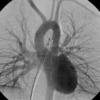

PA angio

Fig 1

Date: 03/23/2004

Views: 3661